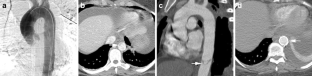

The aim of this study is to describe the frequency, computed tomographic angiography (CTA) imaging appearance, management, and outcome of patients who present with minimal thoracic aortic injury. This retrospective study was Institutional Review Board-approved. Eighty-one patients with blunt traumatic aortic injuries (BTAI) were identified between 2004 and 2008, comprising 23 patients with minimal aortic injury (MAI) (mean age, 43.2 years ±18.2 years; 12 males and 11 females) and 58 patients with non-minimal aortic injury (mean age, 42.6 years ±22.7 years). CTA imaging was reviewed for each patient to differentiate those with MAI from those with non-MAI BTAI. Inclusion criteria for MAI on CTA were: post-traumatic abnormality of the internal contour of the aorta wall projecting into the lumen, intimal flap, intraluminal filling defect, intramural hematoma, and no evidence of an abnormality to the external contour of the aorta. Relevant follow-up imaging for MAI patients was also reviewed for resolution, stability, or progression of the vascular injury. The electronic medical record of each patient was reviewed and mechanism of injury, injury severity score, associated injuries, type and date of management, outcome, and days from injury to last medical consultation. Minimal aortic injury represented 28.4 % of all BTAI over the study period. Mean injury severity score (37.1), age (43.2 years), and gender did not differ significantly between MAI and non-MAI types of BTAI. Most MAI occurred in the descending thoracic aorta (16/23, 69 %). Without operative or endovascular repair, there was no death or complication due to MAI. One death occurred secondary to MAI (4.4 %) in a patient who underwent endovascular repair and surgical bypass, compared with an overall mortality rate of 8.6 % in the non-MAI BTAI group (p = 0.508). The most common CT appearance of MAI was a rounded or triangular intra-luminal aortic filling detect (18/23 patients, 78 %). In a mean of 466 days of clinical follow-up, no complications were observed in survivors treated without endovascular repair or operation. Minimal aortic injury is identified by multi-detector row CT in more than a quarter of cases of BTAI and has a low mortality. Conservative management is associated with an excellent outcome.

Fig. 1

Fig. 2

Fig. 3

Fig. 4